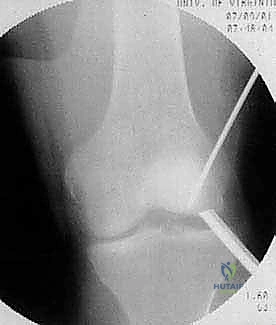

2. التصوير بالأشعة السينية (X-rays)

هي الخطوة التصويرية الأولى والأساسية. يطلب الدكتور هطيف صوراً بوضعيات محددة (أمامية خلفية، جانبية، وضعية النفق Notch view، ووضعية شروق الشمس Skyline view) أثناء الوقوف (تحميل الوزن). تساعد الأشعة السينية في رؤية العيوب العظمية، وتحديد حجم الآفة، واكتشاف أي أجسام حرة (Loose bodies) متكلسة داخل المفصل.